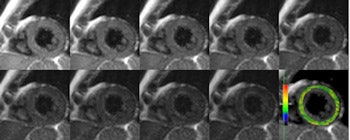

Raw MRI images with corresponding color T2 map in a healthy volunteer, acquired with a Gradient Spin Echo (GraSE) technique using nine gradient-recalled echoes.

The researchers segmented T2 maps generated for each slice according to the American Heart Association (AHA) 17-segment model.